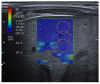

Lung ultrasound (LUS) is, at present, a standard technique for the diagnosis of acute lower respiratory tract infections (ALRTI) and other lung pathologies. Its protocolised use has replaced chest radiography and has led to a drastic reduction in radiation exposure in children. Despite its undeniable usefulness, there are situations in which certain quantitative measurements could provide additional data to differentiate the etiology of some pulmonary processes and thus adapt the treatment. Our research group hypothesises that several lung processes such pneumonia may lead to altered lung tissue stiffness, which could be quantified with new diagnostic tests such as lung sono-elastography (SE). An exhaustive review of the literature has been carried out, concluding that the role of SE for the study of pulmonary processes is currently scarce and poorly studied, particularly in pediatrics. The aim of this review is to provide an overview of the technical aspects of SE and to explore its potential usefulness as a non-invasive diagnostic technique for ALRTI in children by implementing an institutional image acquisition protocol.